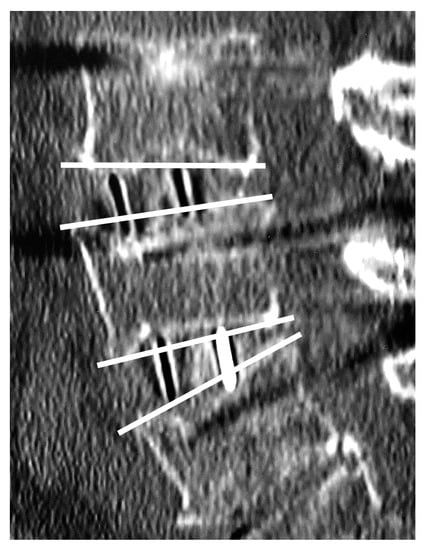

X-ray images were obtained in the standard standing position. CT images were taken using standard methods (Aquilion ONE Nature Edition, Canon, Tokyo, Japan; tube voltage 135 kV), and multiplanar reconstruction (MPR) images were produced. Postoperative CT images of patients who underwent staged surgeries were taken after both scheduled surgeries were completed. For spinal alignment, lumbar scoliosis (Cobb angle), pelvic incidence (PI), lumbar lordosis (LL), pelvic tilt (PT), and sagittal vertical axis (SVA) were measured. Each intervertebral lordotic angle was measured preoperatively and at 1 week and 3 months postoperatively by CT-MPR sagittal imaging. The intervertebral lordotic angle was defined for a positive value for lordosis (Figure 4).

Figure 4. Intervertebral lordotic angle was defined as the angle formed by the cephalad endplate of the upper vertebra and the caudal endplate of the lower vertebra for each level.